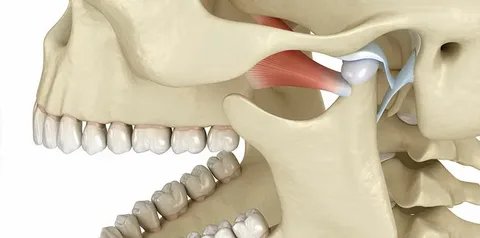

What Exactly Is TMJ? Why Does It Hurt So Much?

Your TMJ (temporomandibular joint) connects your jawbone to your skull and functions like a hinge, allowing you to talk, chew, and yawn.

When it becomes strained, inflamed, or misaligned, it triggers discomfort that can radiate to your head, neck, and ears.